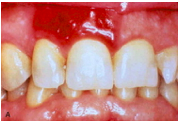

What are oral pyogenic granulomas?

oral masses usually found on the gingiva of children, young adults, and pregnant women. These lesions are highly vascular and often erythematous appearing.

These tend to grow fastly but are typically benign and surgical excision is curative